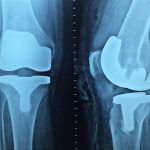

保護膝關節遠離病痛 把握這四個關鍵期

图片来源:Pixabay

作者:北京协和医院骨科 徐启明

膝关节是人体最大、最复杂的关节,也是最大的承重关节。在人漫长的一生中,膝关节的磨损是不可避免、无法逆转的,从学会走路的那一天起,就不停地被磨损消耗。尽管它在我们的生命中发挥着极其重要的作用,它的健康却往往被大家忽视。很多人直到被各种关节病痛困扰时,才想起呵护自己的膝关节,并为年轻时的不当行为后悔不已。那么,要善待膝关节,我们该注意些什么呢?